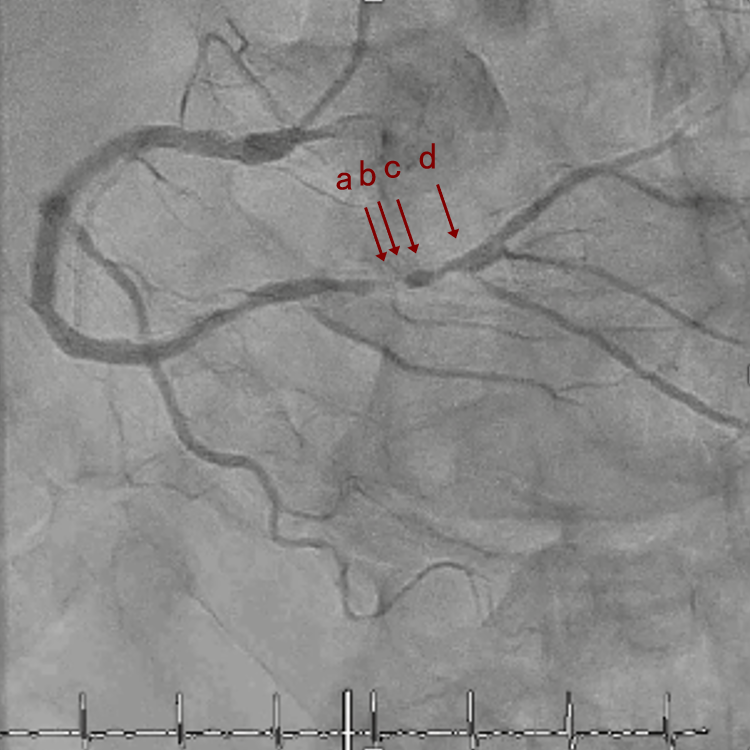

CAG

RCA distalの高度石灰化狭窄病変